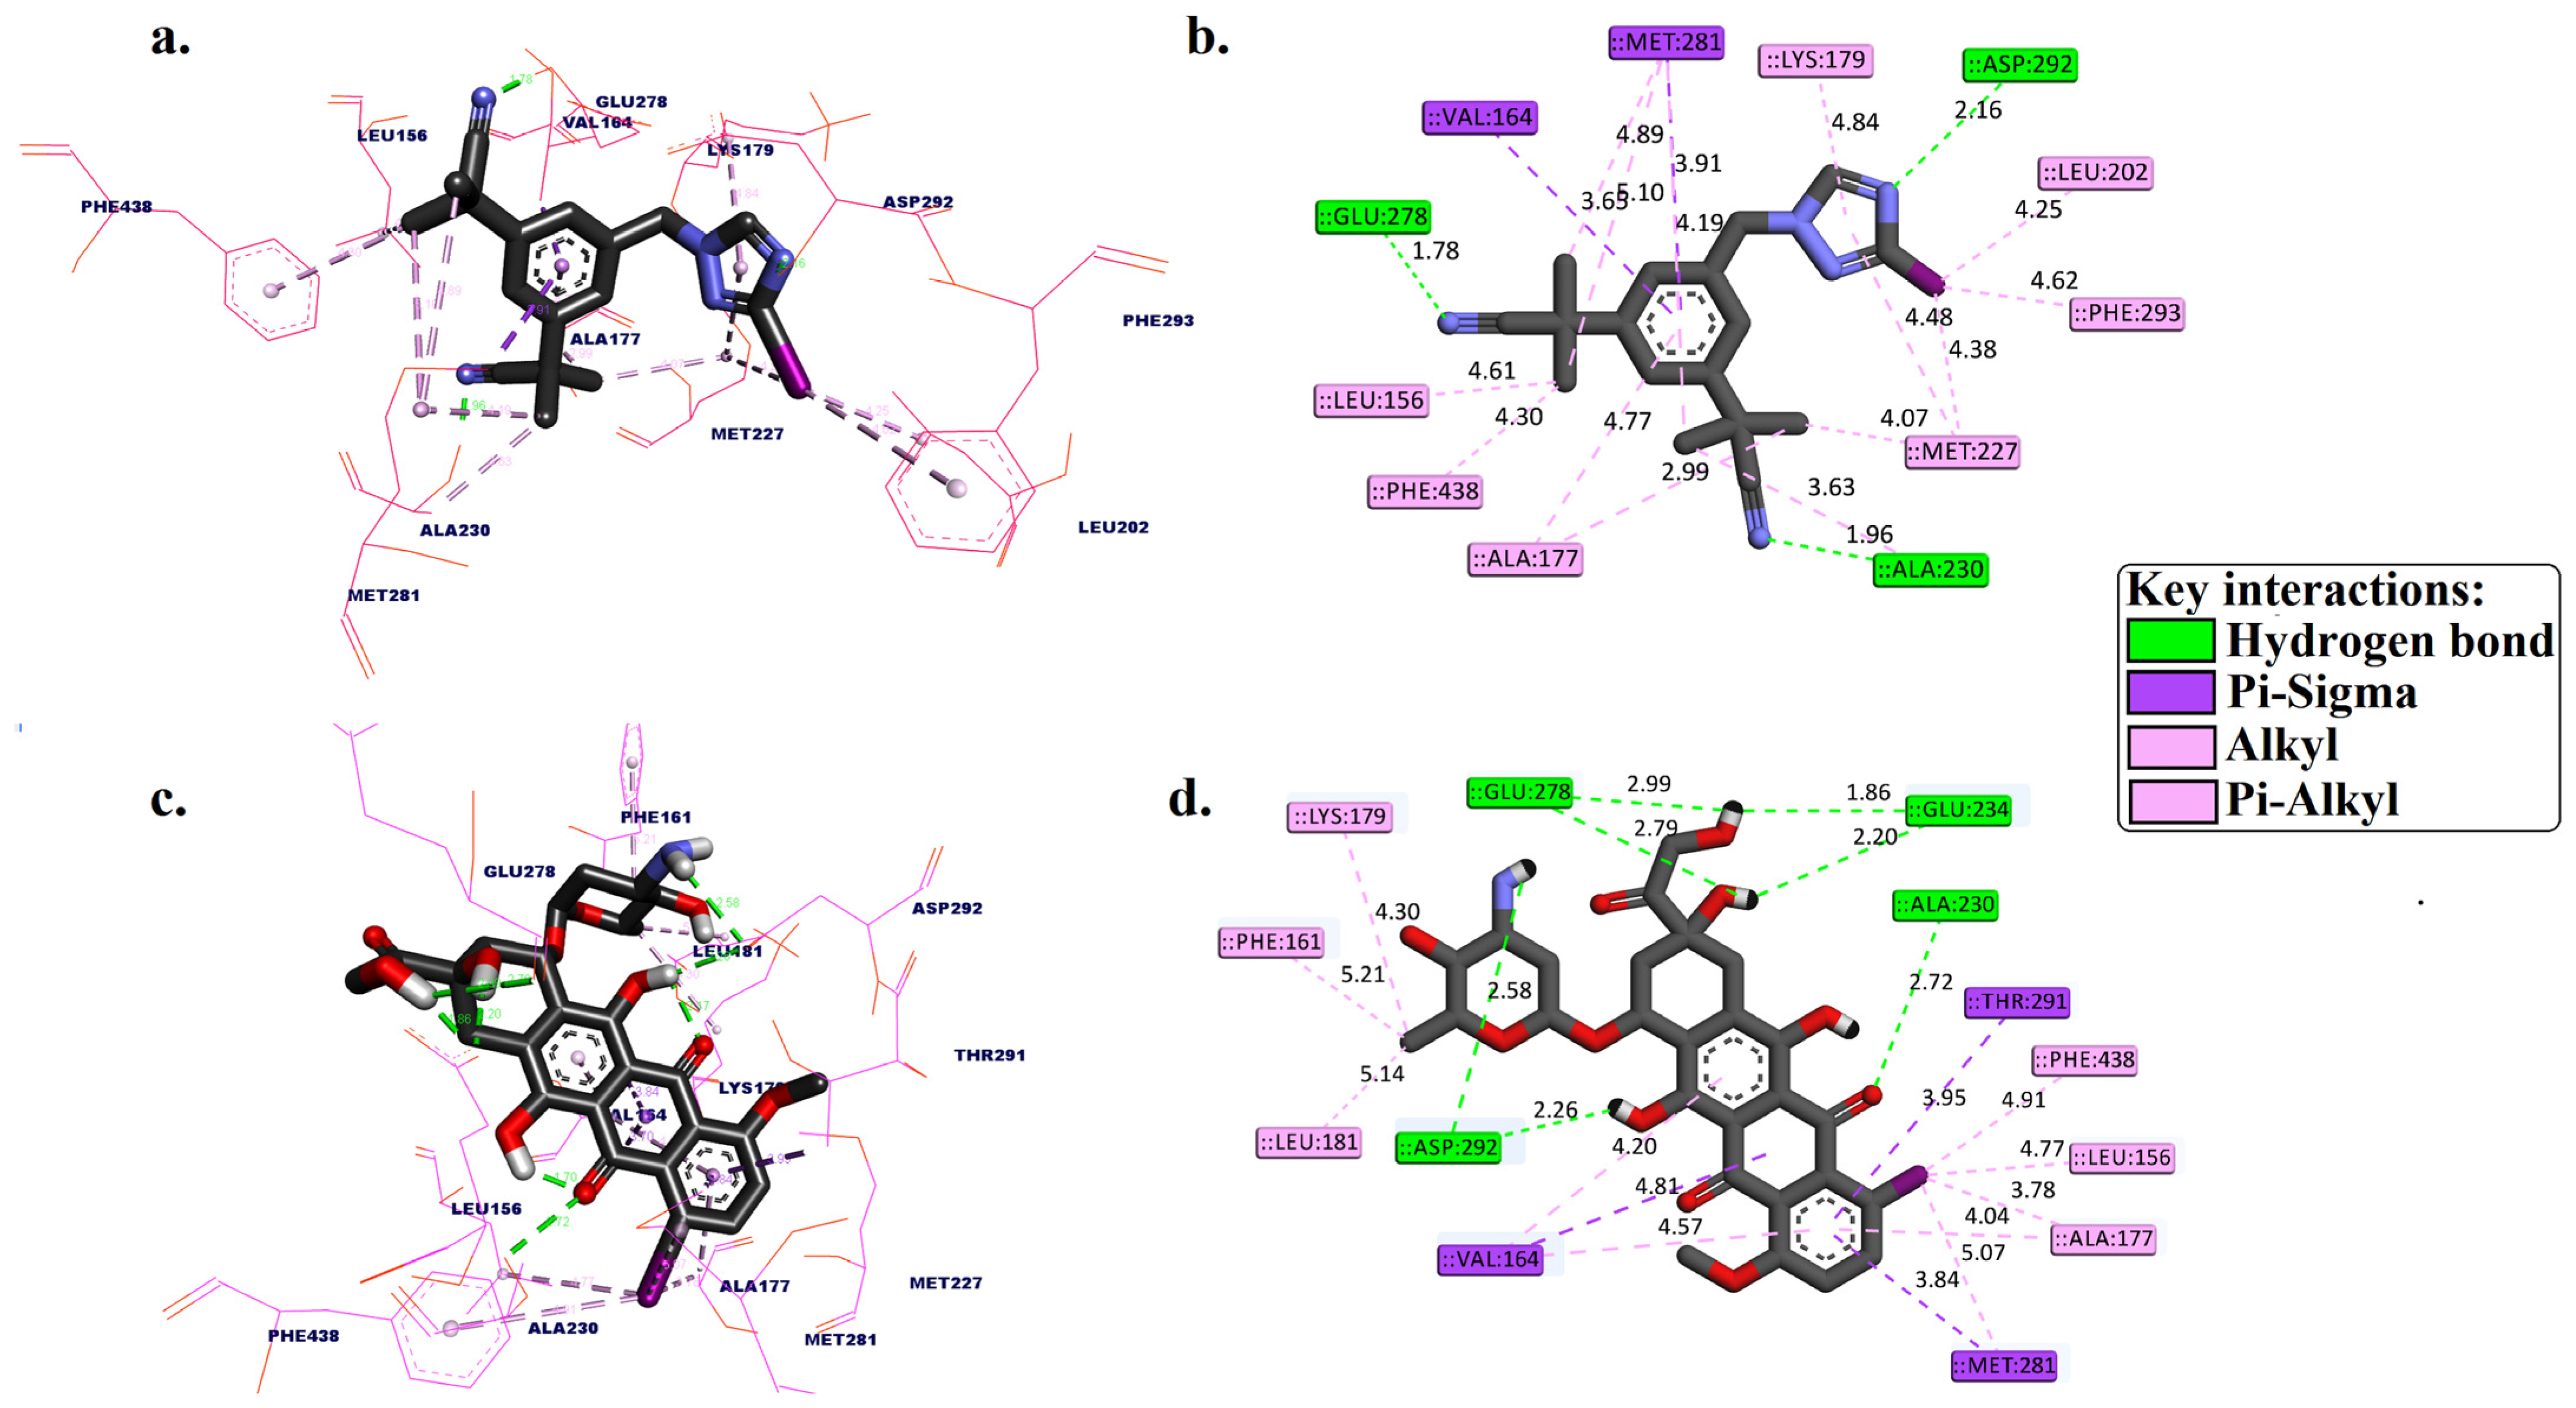

2.1. Molecular Docking

3.1. Molecular Docking Simulation

| Compounds | Free Binding Energy (kcal/mol) | Molecular Interactions Analysis within the AKT1 Active Binding Site | |||

|---|---|---|---|---|---|

| H-bond | Distance (Å) | Pi-Sigma | Hydrophobic Interaction | ||

| [125I]anastrozole | −10.68 | ALA230, GLU278, and ASP292 | 1.96, 1.78, and 2.16 | VAL164 and MET281 | LEU156, ALA177, LYS179, LEU202, MET227, MET281, PHE293, and PHE438 |

| [125I]epirubicin | −11.84 | ALA230, GLU234, GLU234, GLU278, GLU278, ASP292, and ASP292 | 2.72, 1.86, 2.20, 2.79, 2.99, 2.26, and 2.58 | VAL164, MET281, and THR291 | LEU156, PHE161, VAL164, ALA177, LYS179, LEU181, PHE281, and PHE348 |

| * Co-crystalized ligand (original pose) | −9.53 | ALA230 and GLU278 | 1.98 and 2.67 | - | VAL164, ALA177, LYS179, ALA230, and MET281 |